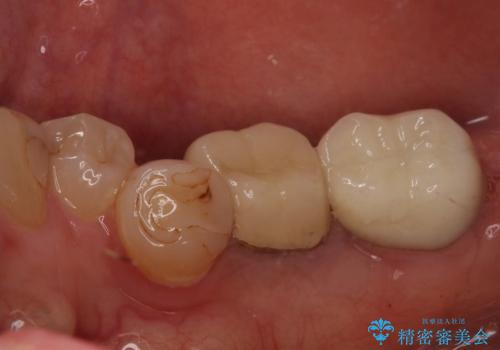

根管治療を行ったは、以前の治療で開けられて思われる穴が歯の内部に開けられており、炎症を起こしていました。

根管治療と合わせて、穴の開けられている部分を修復したところ、炎症による歯槽骨吸収に改善が見られました。